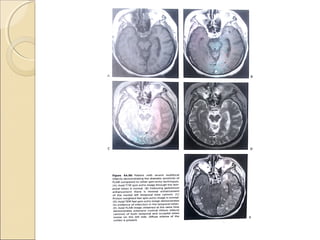

Fluid-attenuated inversion recoveryFluid-attenuated inversion recovery

(FLAIR)(FLAIR)

First described in 1992 and has become

one of the corner stones of brain MR

imaging protocols

An IR sequence with a long TR and TE

and an inversion time (TI) that is tailored

to null the signal from CSF

Particularly helpful in evaluating

periventricular white matter lesion.